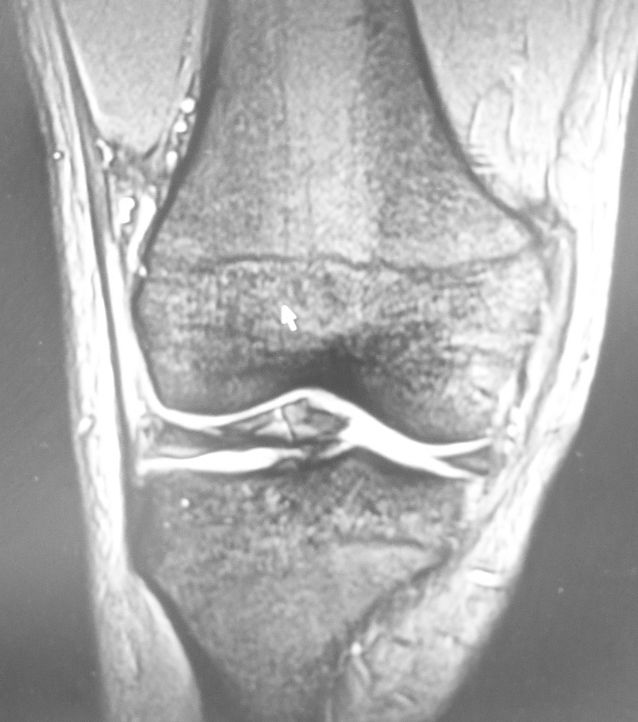

ところで、何故ご本人さえ忘れていたピップエレキバンの存在を、放射線科技師が分かったかというと、下図のようなアーチファクトが発生していたからです。

一見、なんじゃこりゃという所見ですが、よくよく考えてみるとピップエレキバンを貼付したままMRIを撮像した画像をみるのは初めてです。

あんなに小さな鉄粒でも、大きなアーチファクトができるようです。幸い、患者さんに火傷被害はなかったようですが、高齢者の貼り忘れピップエレキバンは要注意だと思いました。